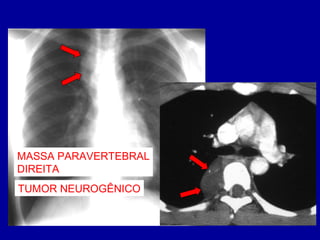

MASSA PARAVERTEBRAL

DIREITA

TUMOR NEUROGÊNICO